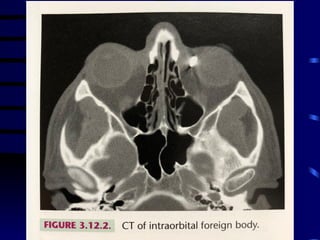

• Normalmente relacionado

com armas de fogo ou

corpo estranho com

grande velocidade

• Orifício de entrada (e de

saída?)

• Raio X pode mostrar a

localização do corpo

estranho (metálico)

• Localização difícil – USG

ou TC

TRAUMATISMO OCULAR PENETRANTE •Normalmente relacionado com armas de fogo ou corpo estranho com grande velocidade • Orifício de entrada (e de saída?) • Raio X pode mostrar a localização do corpo estranho (metálico) • Localização difícil – USG ou TC